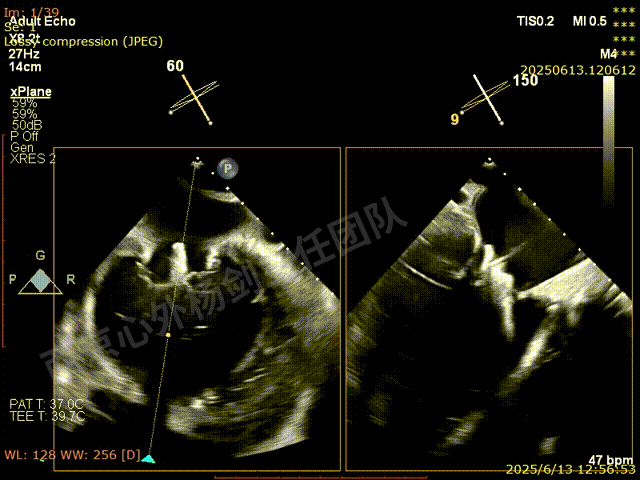

夹子关闭后检查夹子两侧反流

第一枚XTW释放后评估,外侧反流基本消失,内侧仍然有中度以上反流

第二枚XT于第一枚夹子内侧瓣上调整